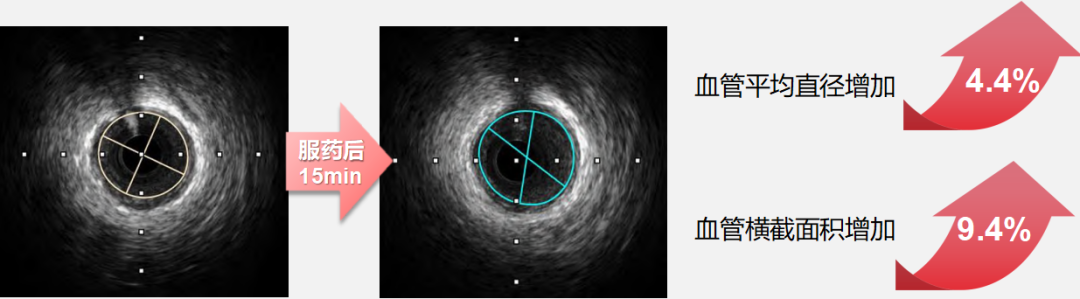

●而速效救心丸展现出 “精准化” 的血管调控特征:对直径 2.00-2.75mm 的细小冠状动脉扩张作用更突出,服药后15 分钟该直径区间血管横截面积面积扩张百分比最高可达 8.58%(如下图),且扩张过程中患者血压、心率等血流动力学指标无显著波动。

1774487391524189.png